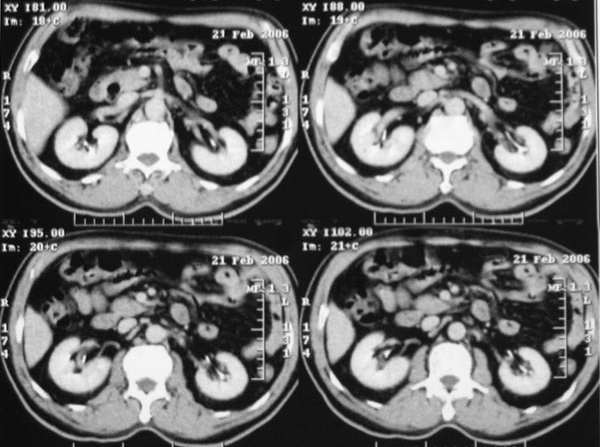

患者,m,71y,乏力、纳差、巩膜黄染两月余,b超示肝内占位性病变。

平扫

动脉期

门脉期

延时期

3、门脉期:病灶呈低密度,低于肝实质,下腔静脉见充盈缺损,说明癌栓形成

综上所述,符合肝癌伴下腔静脉癌栓形成

门脉期下腔静脉内可見充盈缺损,考虑栓塞,应考虑为恶性病变,旰癌可能性大